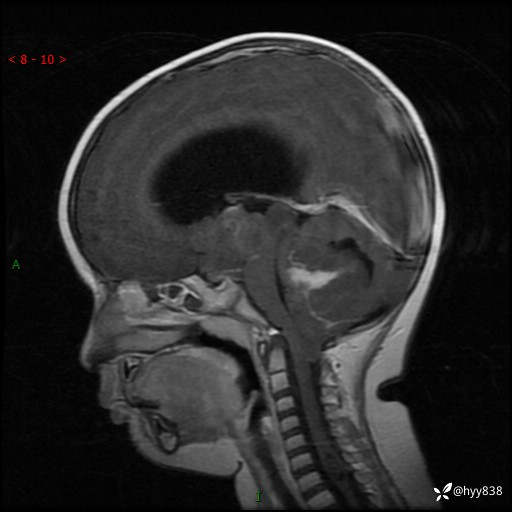

理解“经典”,从经典病例开始,3岁小女孩,行走不稳2个月,加重1个月--结果公布

性别:女

年龄:3岁

简要病史:发现行走不稳2个月,加重1个月

颅脑MRI平扫+增强